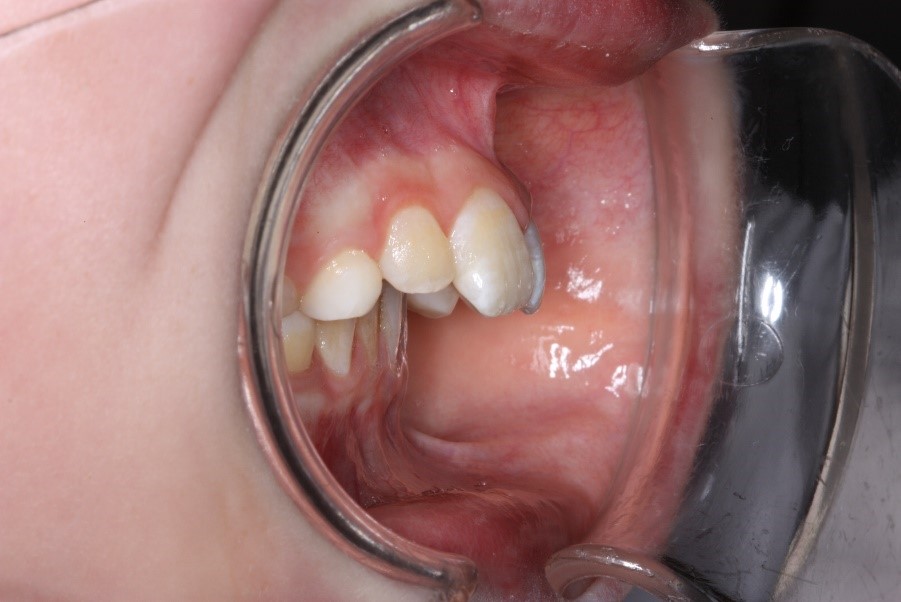

- wenn durch weit vorstehende obere Schneidezähne (s. Abb. 2) oder einen weit zurückliegenden Unterkiefer eine Verletzungsgefahr für die bleibenden Schneidezähne besteht. Die Lippen bedecken dann nicht mehr schützend die Zähne, sodass im Falle eines Sturzes die Zähne größeren Schaden nehmen können.